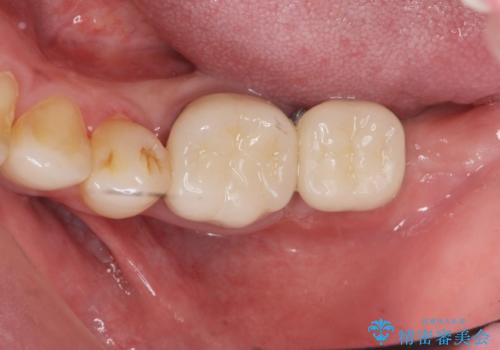

最後方臼歯の治療について

最後方臼歯を喪失した場合、入れ歯・インプラントによる咬合機能回復方法があります。

今回はしっかりと噛むことができ、取り外しの必要のないインプラントによる補綴を行いました。